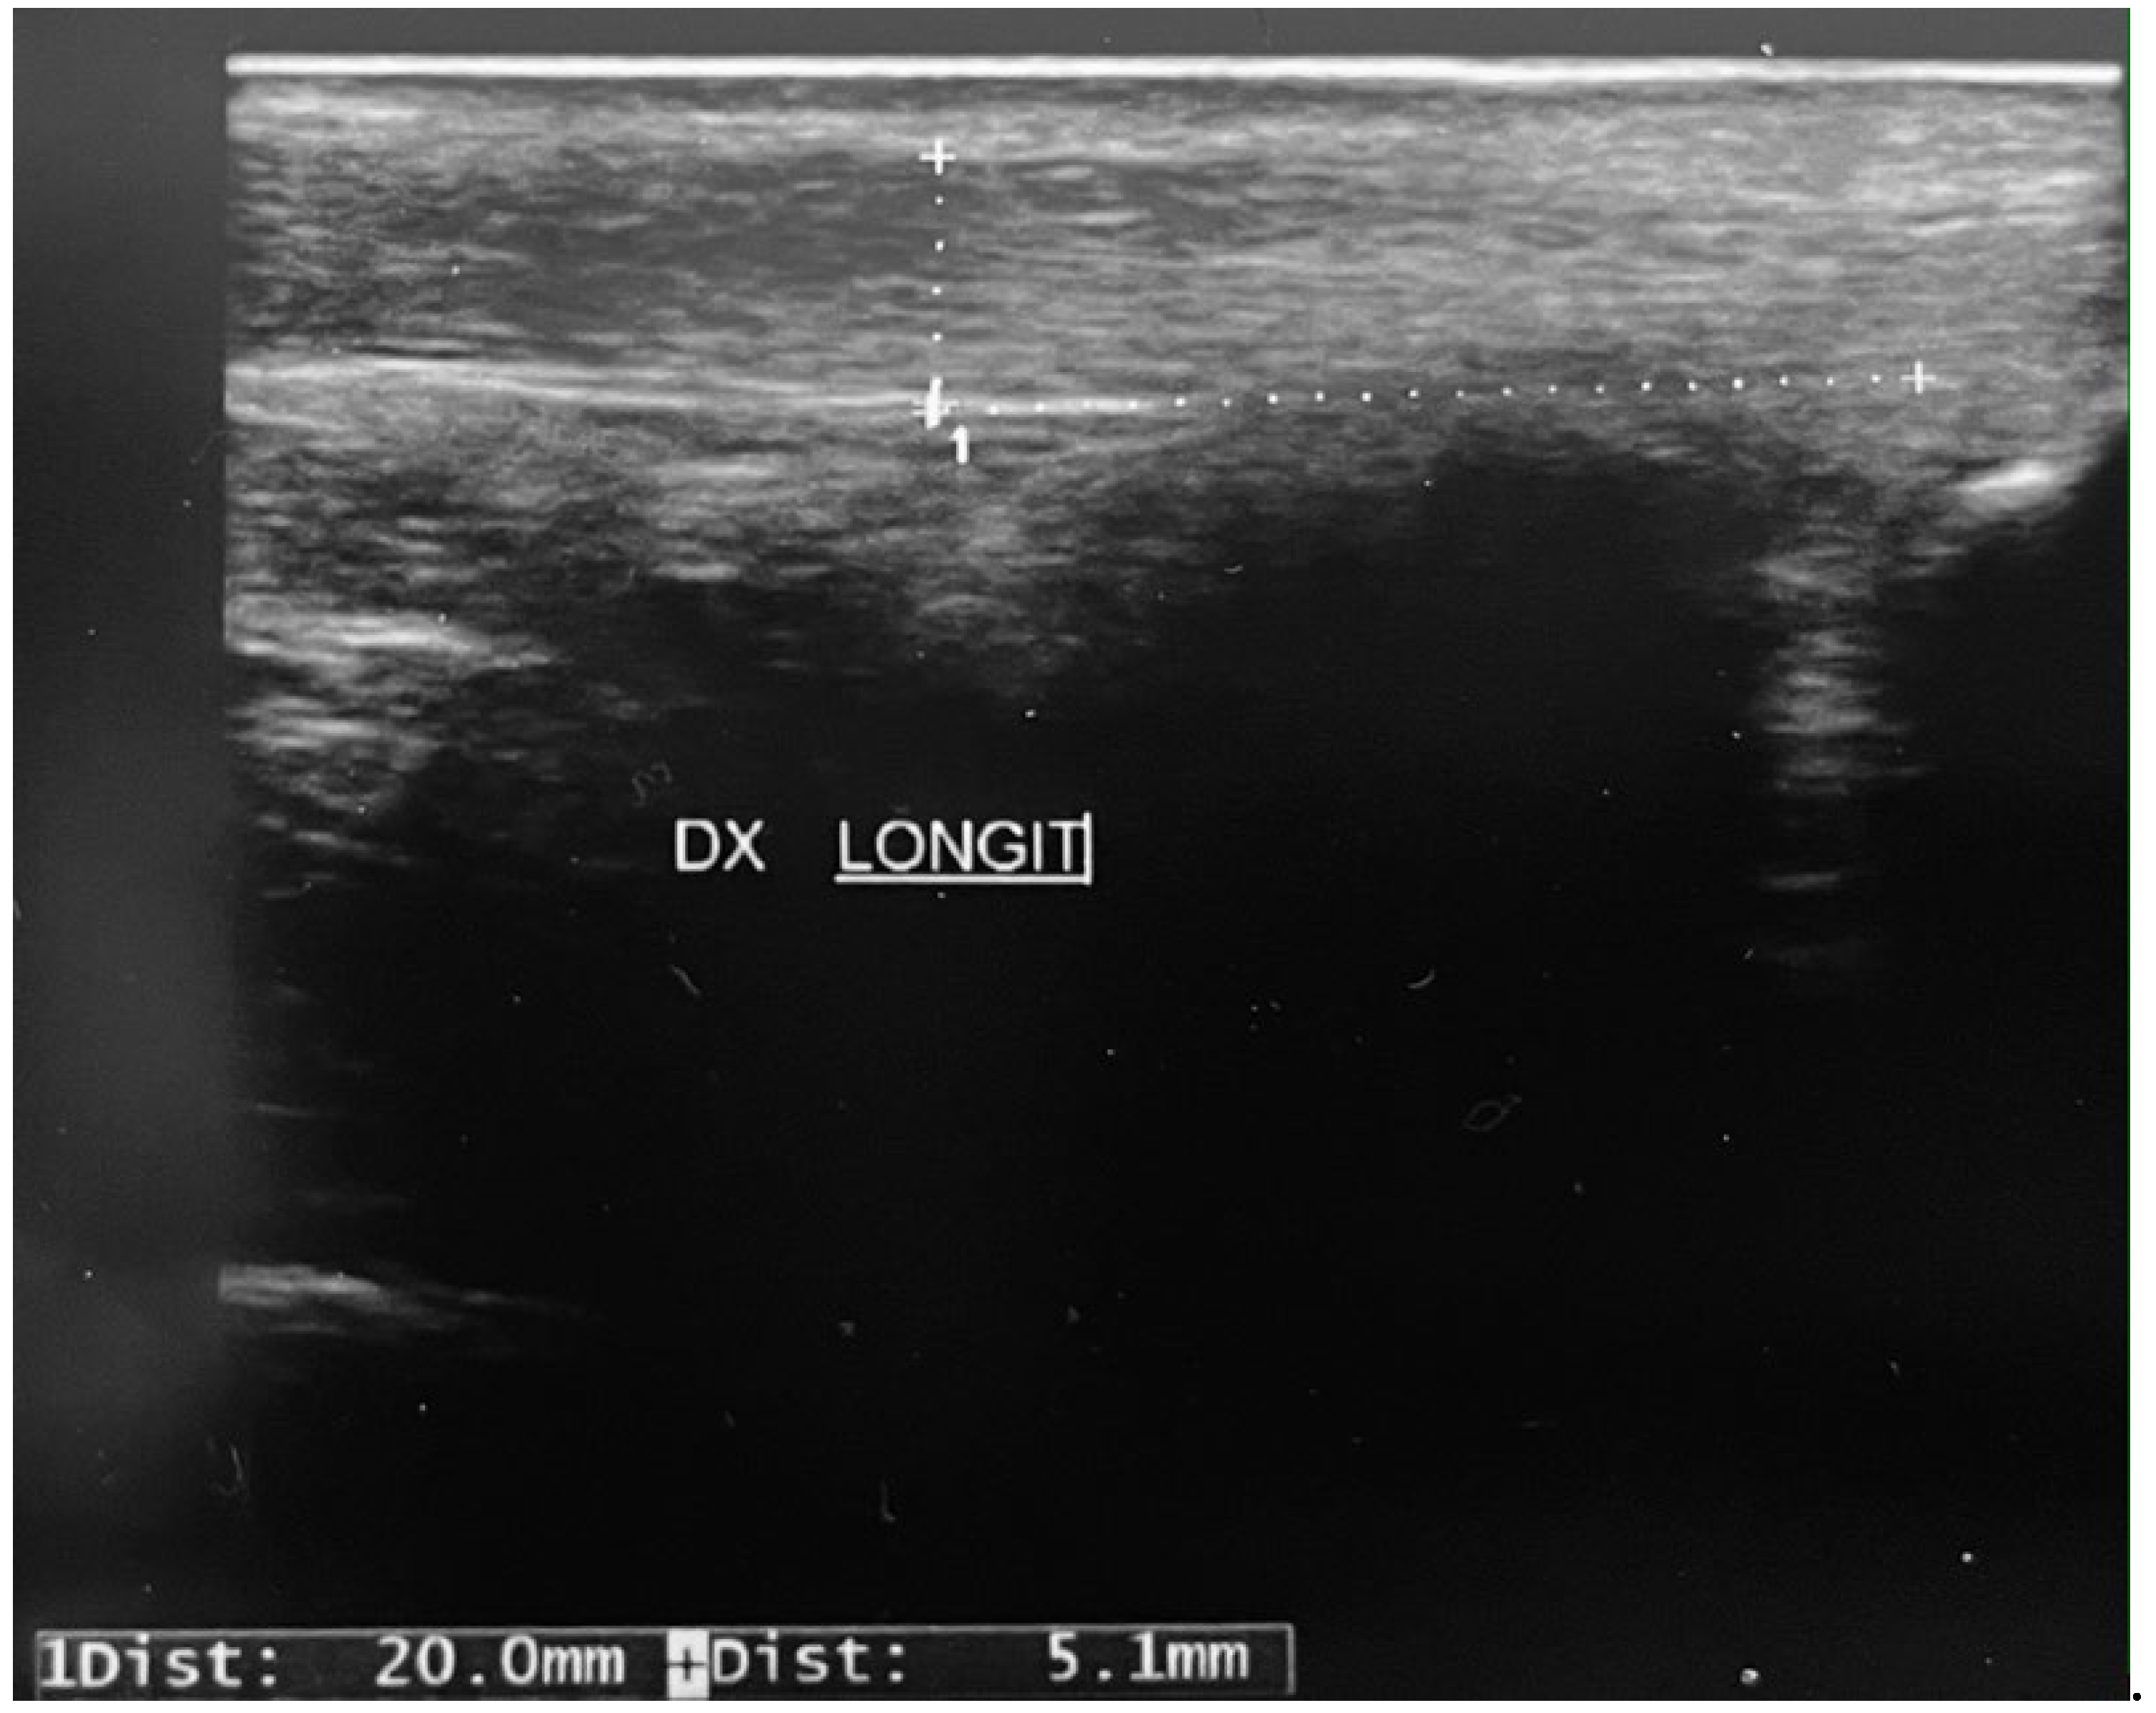

The examination was carried out by the same operator with a Hitachi Arietta 65 ultrasound machine using a linear probe. Because tissues of fibrillar structure, such as tendons, have reduced echogenicity based on the angle of the transducer, attention was paid to the correct positioning of the probe, to avoid mistakes in interpretation of pathological defects. Patients layed in the prone position with the ankles extending over the edge of the table. Each foot was studied both in neutral and in dorsiflexion position. Tendon images were viewed in real-time in longitudinal and transverse planes; the section site was identified 2.0 cm above the calcaneal insertion. Diffuse or localized hypoechoic areas in the superficial layer of the tendon, near the perithenonium, and the presence of calcifications were sought. Areas of vascularization and the number of vessels present were evaluated by means of color Doppler ultrasound.

A surgical procedure on the Achilles tendon (tenotomy or Z-lengthening) is an integral part of the treatment of clubfoot [8,9,12,13]. We investigated ultrasound parameters in the Achilles tendons of asymptomatic patients treated in the past for congenital clubfoot. Statistically significant observed data were a greater thickness of the operated tendons compared to those treated with plaster alone (with no difference between the tenotomized ones and those with Z-plasty); furthermore operated tendons presented structural alterations, with a greater presence of hypoechoic areas. These ultrasound characteristics are similar to those observable in case of tendinopathy, even in the absence of subjective symptoms. Our results are different from those observed by other Authors, which have documented tendon healing within a few weeks after tenotomy, observing minimal ultrasound anomalies during follow-up, that did not seem to affect function [14,17,24,25]. The Authors however report data at a shorter distance from the operation, at 6 and 4 weeks respectively [14,26]. Furthermore, during the collection data, one of the patients analyzed in our study suffered a rupture of the right Achilles tendon, as she walked (Figure 2). The patient was a volleyball player, she was in good health, she had taken any medications, in particular quinolones, and she had no other risk factors for tendinopathy. The ultrasound we previously carried out showed a thickening of the Achilles tendon and diffusely hypoechoic superficial areas (Figure 3) 2 cm from the insertion on the calcaneus. Few cases of subcutaneous rupture of the Achilles tendon, in adolescent undergoing Achilles tenotomy for clubfoot, are described in the literature. Since in adolescents there are usually no intrinsic factors predisposing tendinopathy, tendon alterations underlying subcutaneous rupture could be attributed to the previous surgery, as hypothesized by the other authors [27,28].

Figure 3. The ultrasound finding shows a thickening of the Achilles tendon and diffusely hypoechoic superficial areas 2 cm from the insertion on the calcaneus.